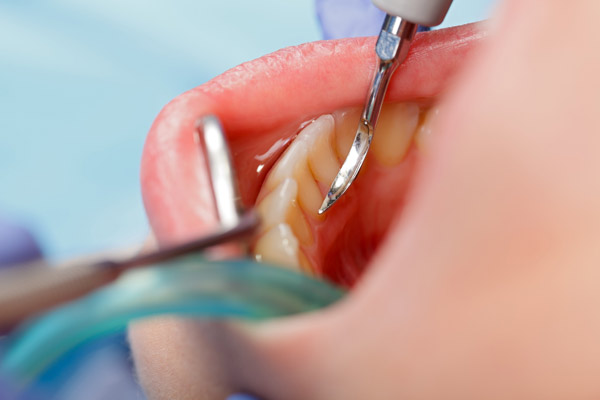

Nhưng hiện nay, kỹ thuật lấy cao răng mới dùng sóng siêu âm của đầu dụng cụ scaler, làm rung lên để vôi bám vào men răng rớt ra, làm cho răng trở nên sáng hơn. Đây là kỹ thuật rất đơn giản, chỉ tác động vào mảng cao răng và làm bong ra khỏi răng mà không gây tổn thương cho lợi và răng.

Đây là câu hỏi chúng tôi phải thường xuyên trả lời cho khách hàng tại PhamDuong Dental Studio. Lấy cao răng tưởng chừng đơn giản nhưng lại phải thuần thục và có kỹ thuật lấy cao răng tốt mới không gây đau cho khách hàng và tổn thương cho men răng.

Ngoài ra, để lấy cao răng được an toàn, tất cả các dụng cụ và thiết bị phải được tiệt trùng và là thiết bị hiện đại nhất.